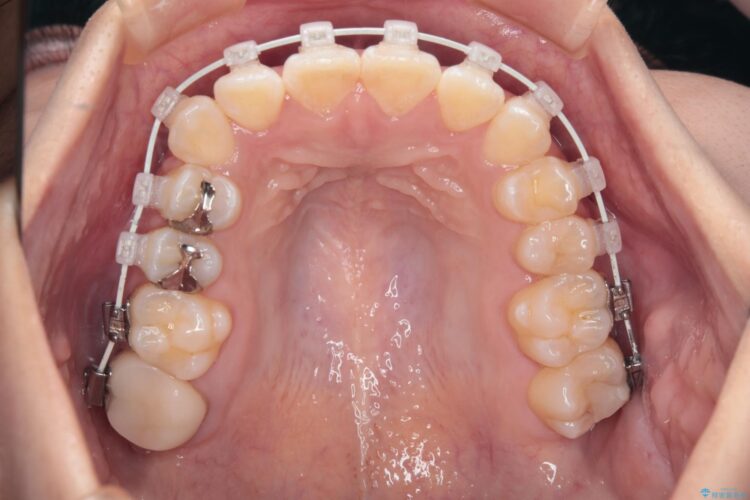

右側の八重歯の部分は噛み合わせをよくするためにゴム掛けを行いました。

また、セラミックと銀歯の部分は装置が脱離してしまうので、矯正用の仮歯に変えて治療を行いました。

予定通り1年で気になっていた八重歯とガタつきが改善され、大変喜んでいただけました。